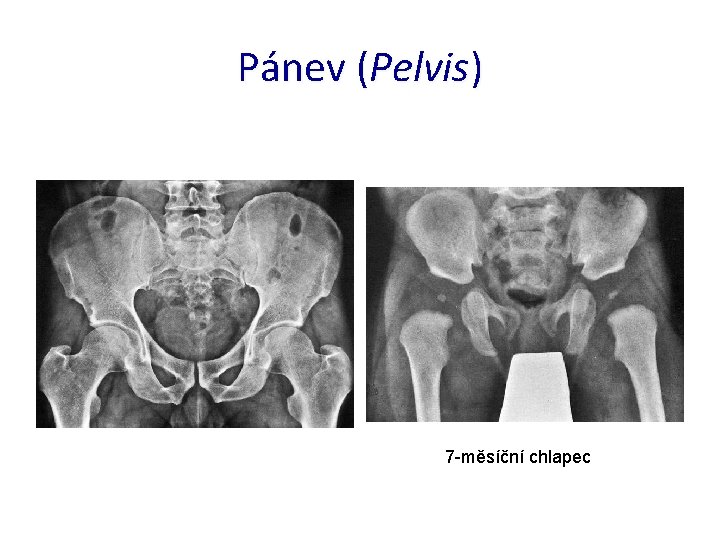

Pánev (Pelvis) 7 -měsíční chlapec